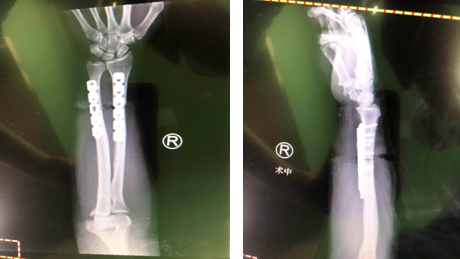

术后钢板内固定